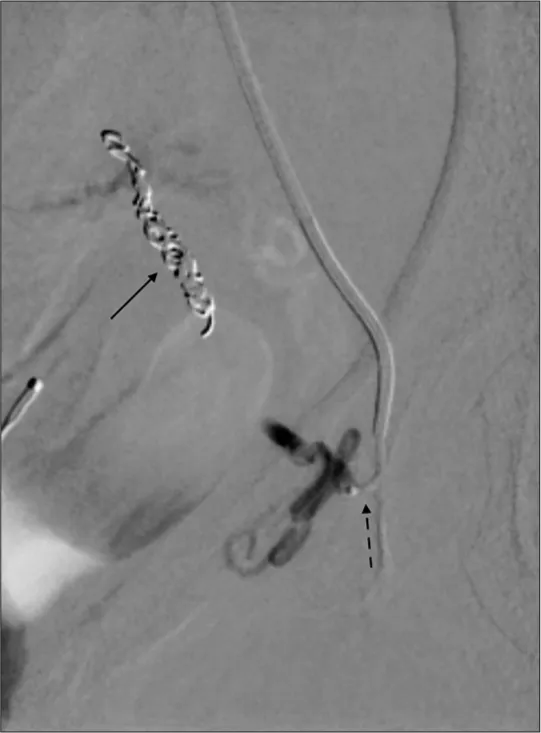

- Mechanical Devices:

- Coils (Platinum, Steel): Fibered or bare. Induce thrombosis, mechanical block.

- Vascular Plugs (e.g., Amplatzer): Nitinol mesh. For larger vessels, precise.

⭐ For effective vessel occlusion, coils should be 20-30% larger in diameter than the target vessel to ensure stable placement and prevent migration.